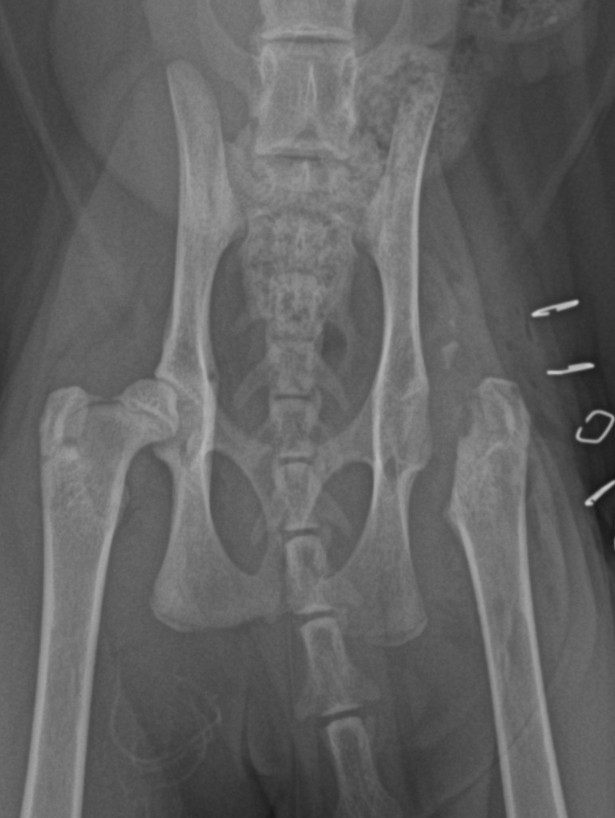

Nekróza krčku stehenní kosti u kočky - FHO

Případy z praxe

Akutní

případ